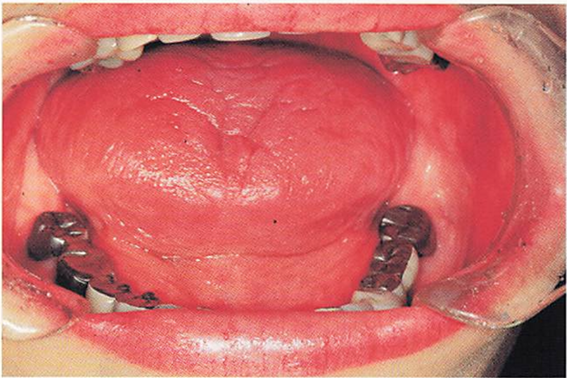

午前-52

54歳の女性。舌の異常を主訴として来院した。2週前に着色を自覚したが、疼痛がないため様子をみていたという。現在、気管支喘息、市中肺炎、 高血圧症および糖尿病に対して薬物療法を受けているという。初診時の口腔内写真 を別に示す。 原因と考えられるのはどれか。2つ選べ。

a.降圧薬

b.抗菌薬

c.血糖降下薬

d.副腎皮質ステロイド薬

解答を見る

b.d